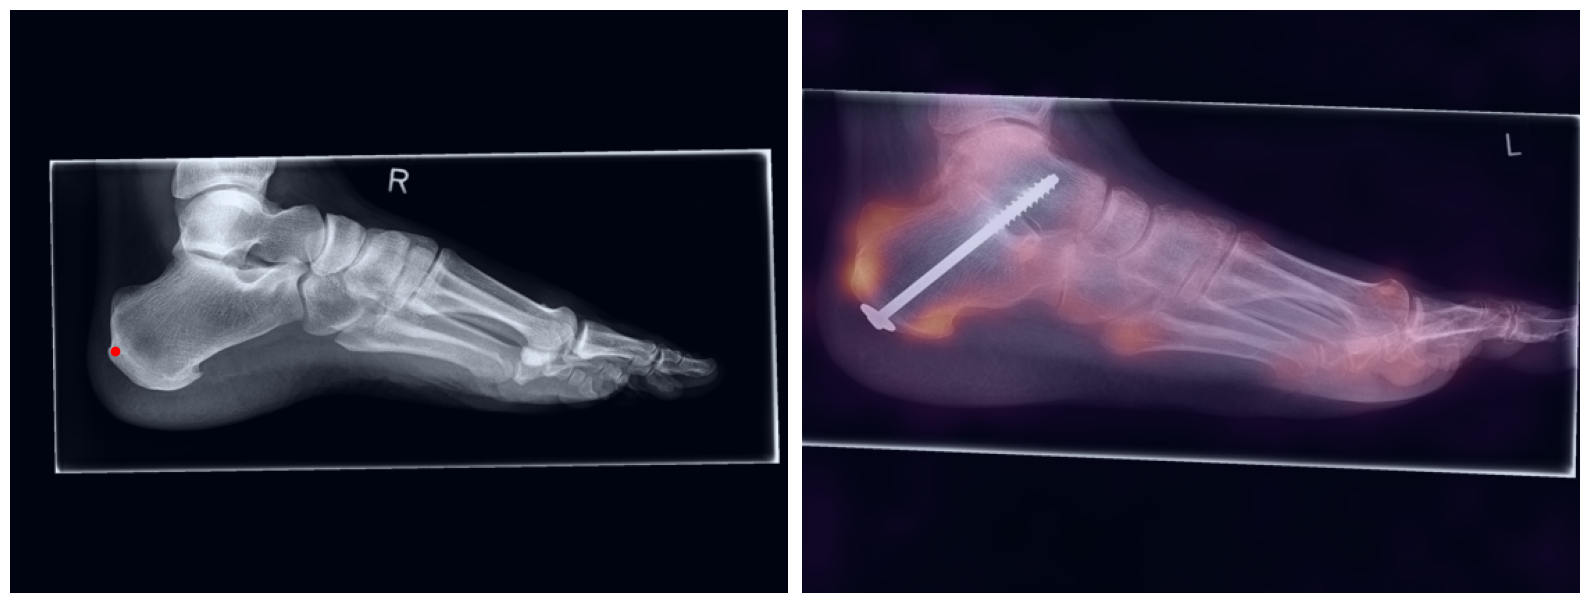

Artificial intelligence (AI) has shown great potential in assisting radiologists with musculoskeletal (MSK) assessments across various anatomical regions1,2,3,4. However, most existing tools are narrowly tailored for specific anatomies or rely on segmentation-based methods as a basis. To address these limitations, we propose a versatile and generalist AI-based approach for landmarks matching. In contrast to typical generalist landmark matching approaches that depend on automatically identified, optimally descriptive landmarks5,6,7, our use-case has to be based on manually selected landmarks tailored for MSK measurements. As these landmarks are potentially subotimal for precise matching, we employ an AI-based method8 that first performs multi-scale dense image matching between the reference and target images independently of the landmarks. The AI uses a combination of transformer and convolutional neural networks to establish a multi-resolution descriptive feature representation of each position within the images, allowing to define correspondences between the reference and target images. In a subsequent step, landmark positions are transferred to the target image based on these correspondences, with the determination of final locations benefiting from the redundancy of the dense matching. This enables robust automation of landmark matching from a reference patient across an entire cohort of target patients. The approach is anatomy-agnostic, enabling the use of the same backbone model for a wide range of anatomical regions and MSK measurements. For more detailed information we refer to our paper.

Once a correspondence between the reference and target radiographs is established, landmark matching can be performed in real-time. This process enables the alignment of individual points and allows for the definition of a predefined set of landmarks that can be mapped onto the target patient. These predefined landmarks can be customized for the automated calculation of specific measurements, which, once defined on a reference patient, can be consistently and automatically transferred to any radiograph within the target cohort.

The process of establishing a dense match between two images relies on abstract feature representations for each position in both the reference and target images. To better understand which information is encoded by the AI, we examined the feature similarities between a specific position within the reference image and the entire target image. Our findings show that the AI captures both semantic and texture features. The matching process utilizes this encoded information, along with precise positional data, to create a reliable mapping between the images.

From Novice to Expert: Annotation Through Imitation